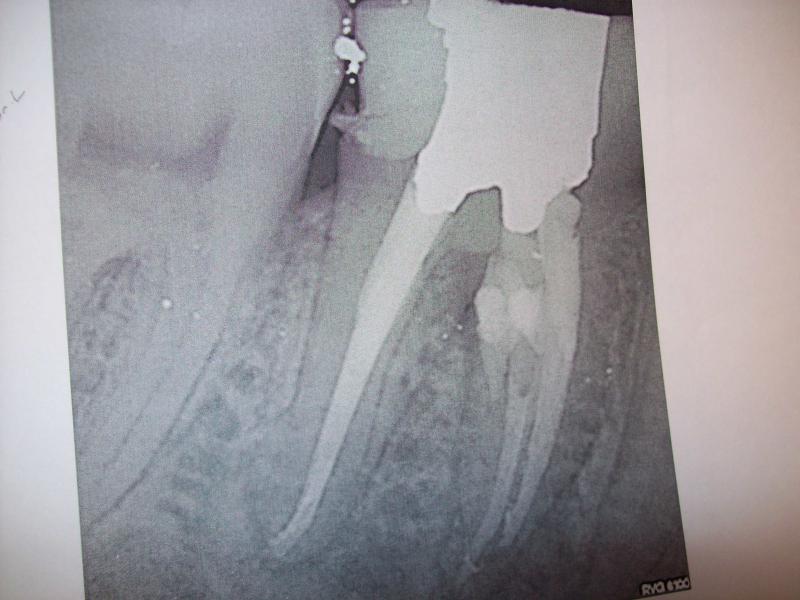

DR JET LOVES ROOT CANALS

General Dentist,  Performs Root Canals ONLY - Microscope Trained Dentist

"DR. JET'S MISSION IS TO PERFORM  ROOT CANALS FOR A REDUCED FEE USING THE LATEST TECHNOLOGY  AND TECHNIQUES TO SERVICE THE MANY PEOPLE WHO ARE UNINSURED OR UNDER-INSURED GIVING EVERYONE AN OPPORTUNITY TO SAVE THEIR TOOTH!"

**PLEASE BE AWARE THAT  A ROOT CANAL IS AN ATTEMPT TO SAVE YOUR ALREADY DAMAGED TOOTH.  THERE IS NO GUARANTEE THAT ANY TOOTH CAN BE SAVED BUT DR JET WILL DO HIS BEST TO HELP YOU. THE OTHER OPTION IS TO EXTRACT YOUR TOOTH